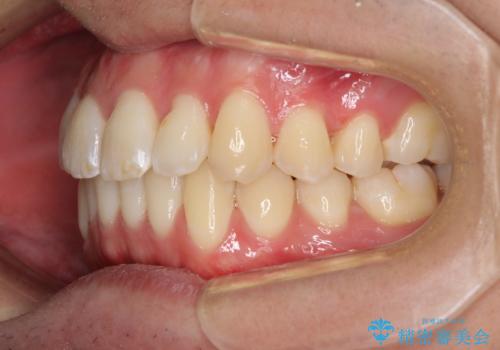

- 前歯のデコボコと若干口元が突出していることを気にして来院された患者様です。

全体的に軽微な叢生が認められ、口元もやや前方に突出していたため、インビザラインでのIPR(歯と歯の間を削る)と歯列全体の後方移動によって歯並びを整えることとしました。

上下ともに歯列の幅が狭かったため、側方に拡大することで前歯のデコボコや突出感を解消するためのスペースを獲得することができました。

歯並びが改善したことはもちろん、咬み合わせの改善まで実感することができ、患者様には大変満足していただけました。